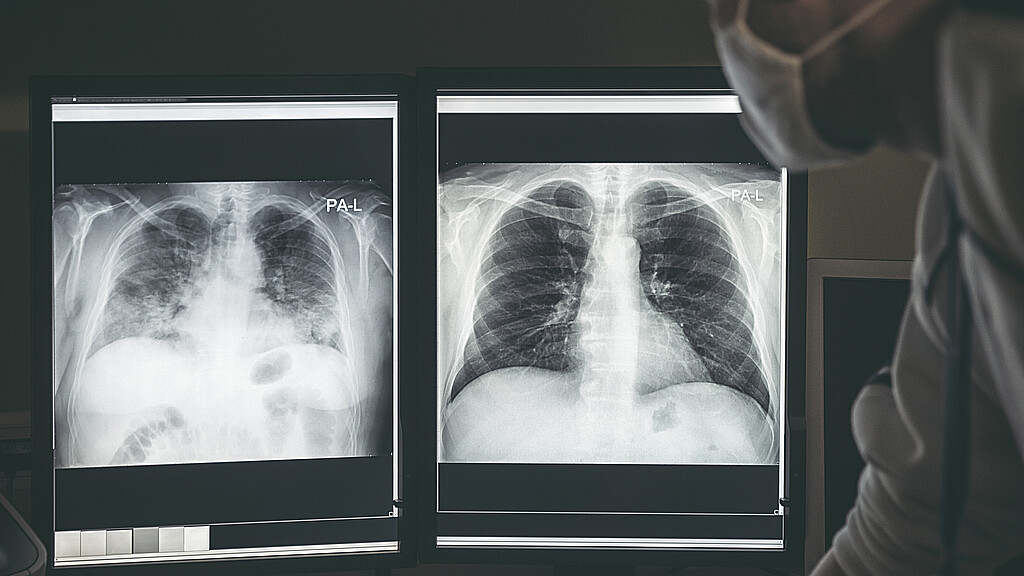

Lo llevaron al hospital donde le tomaron una radiografía que reveló que tenía la dentadura postiza de 1,5 pulgadas atascada en las vías respiratorias de su pulmón, según el estudio de caso publicado esta semana en la revista médica Cureus.